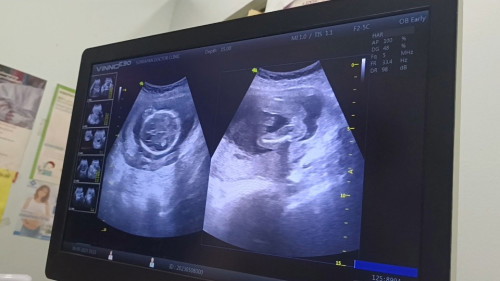

ท้อง2แล้วค่ะ อยากได้ลูกสาว ผลซาวด์ออกมาคุณหมอบอกว่าได้ผู้หญิง แม่ดีใจมากค่ะ เพื่ออยากเพิ่มความมั่นใจ มีใครดูออกไหมคะว่าแบบนี้ผู้หญิงหรือผู้ชาย